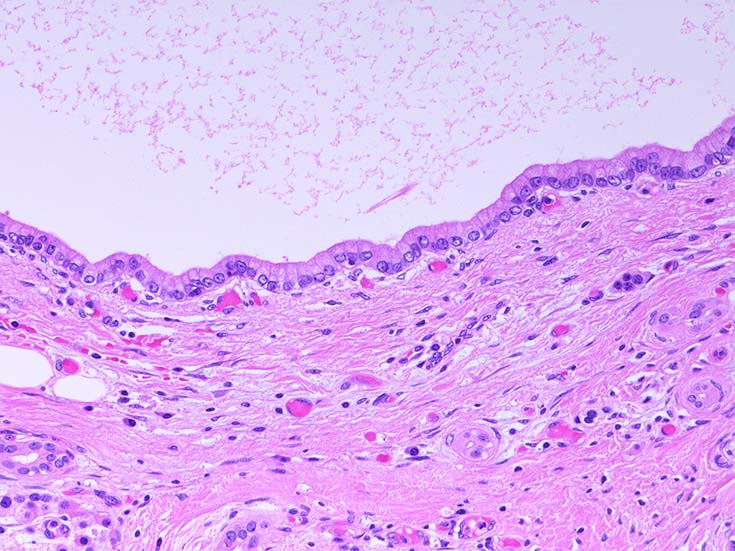

膵上皮内腫瘍性病変 pancreatic intraductal neoplasm(PanIN)*16

Low-grade PanINとhigh-grade PanINの分類

low-grade PanIN

PanINの図譜はJohns Hopkins The Sol Goldman Pancreatic Cancer Research CenterのHome page*19から引用.

1. PanIN-1; PanIN発生の初期段階. 組織学的に, 核異型を伴わない, 核の極性が保たれている.